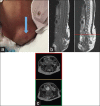

Surgical management of lipomyelomeningocele in children: Challenges and considerations

Figures